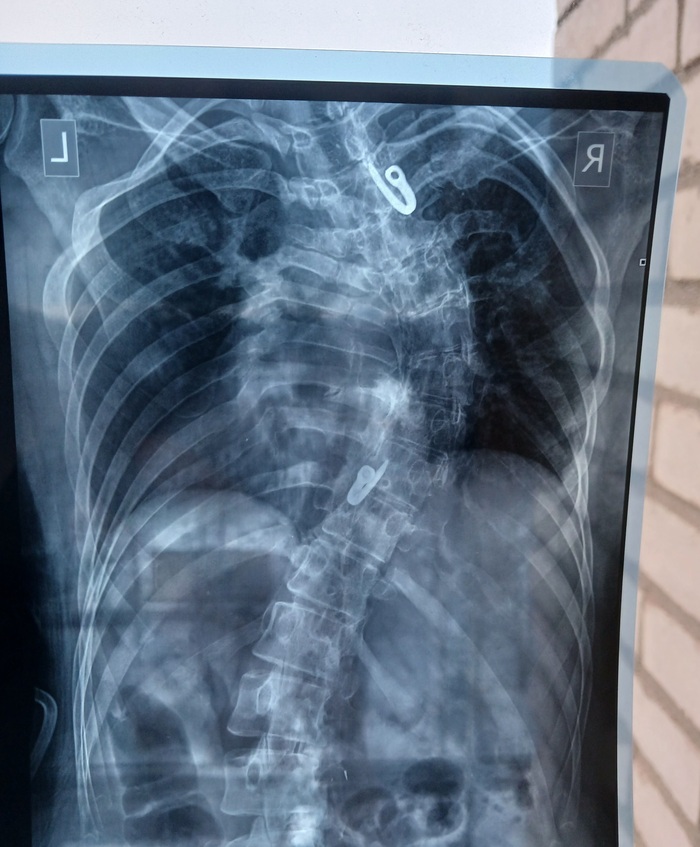

Сколиоз развился около десяти лет, диагноз идиопатический сколиоз. 4 степени.

На момент обследования и фото мне было 13 лет, операцию делали через пол года. и через год после этого "пришла слава" в виде публикации статьи с моим случаем.

Операция "спаивания" (spinal Fusion). Вкратце выкручивали позвоночник в правильном направлении металлическими пластинами. С помощью долота и отверток хахах.

Моя спина попала в учебное пособие по коррекции сколиоза, когда я ездила в Европу на операцию )) Операция прошла успешно )

Когда трава была зеленее, деревья высокие, а мне стукнуло 12, обнаружился у меня сколиоз. Это искривление позвоночника, да не простое, не золотое (хотя, судя по тому, сколько было влуплено в мою спину, платиновое). Короче, S-образное. И понесли ботинки Лилю по всевозможным спорткружкам, массажам, лфк, методикам Бубновского, Дикуля, Хуикуля, потому что врачи уверяли, что спорт укрепляет мышечный каркас, и спину косоёбить не будет. Спойлер: будет. И ещё как. В МОЕМ СЛУЧАЕ!

Причины сколиоза не выявлены до сих пор. Травм у меня не было, все родственники до 7 колена ровные как струнки, одна я кривая, что турецкая сабля. Итого. В 15 лет меня скосило до 76°, в подарок – два горба😁 3 года упорных тренировок ушло в жопу. И в горбы.

А, ну так вот. В 15 лет (2006 год) меня прооперировали, поставили титановую конструкцию. Стоила эта хрень 33700. Как щас помню.

Это было не больно, это было ПИЗДЕЦ КАК БОЛЬНО!!! Я не знаю, как я тогда выжила, наверное, на силе духа. Больно было даже укрыться простынкой, а кашлять без слез получилось только через полгода. Чихать спокойно смогла через год. Похудела в больнице на 10 кг. Выросла на 5 см. Ещё где-то 3-5 осталось. Сейчас рост 174. Вот фоточки

Это до